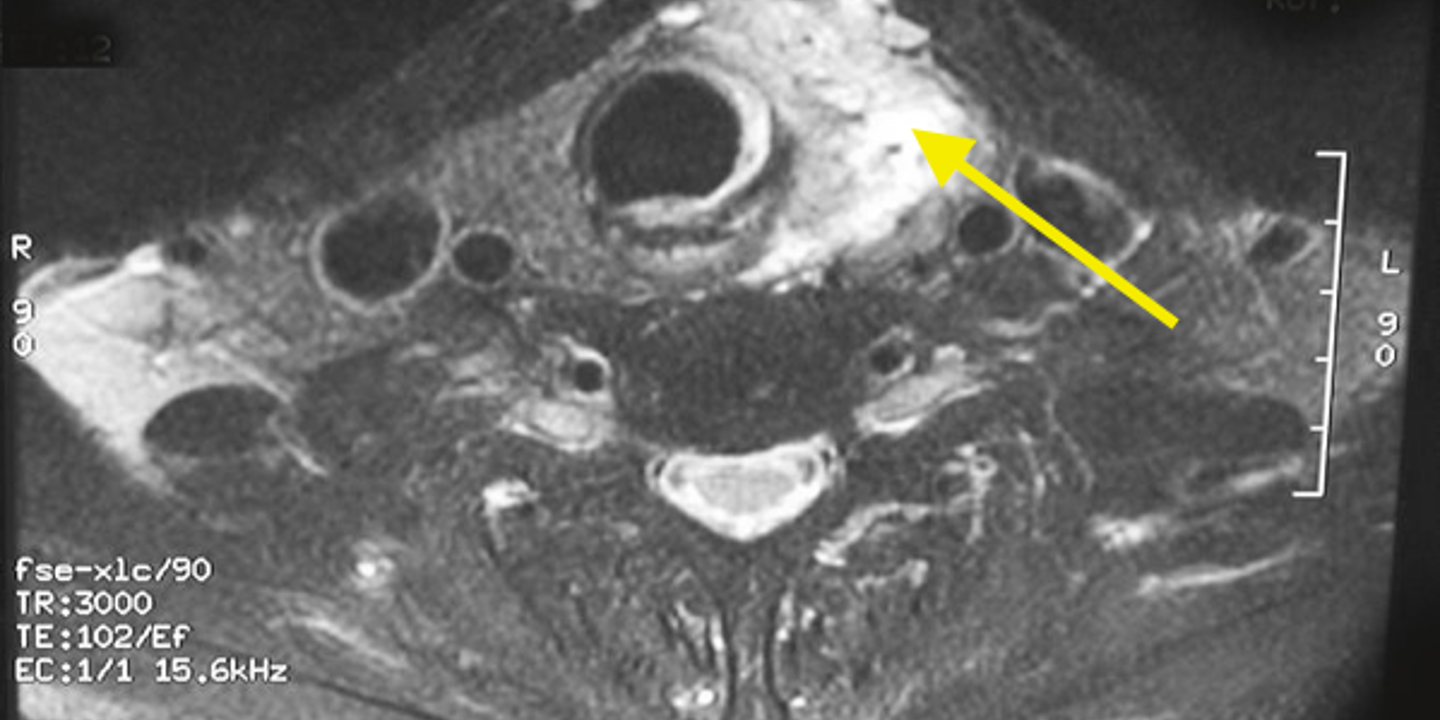

A CT Scan

CAT or CT (computed tomography) scans use advanced X-rays to give your physician a better view of your thyroid. It displays the location and size of a potentially cancerous lump, as well as informs your doctor if cancer has spread to other parts of your body.